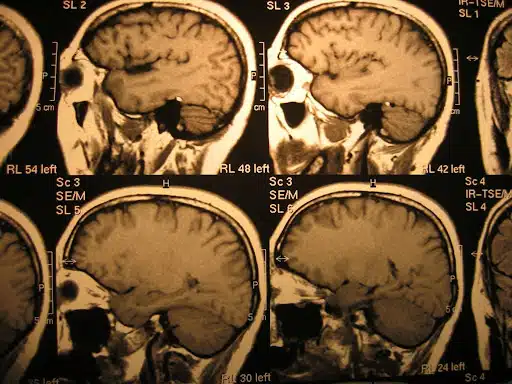

Brain Stroke

A stroke occurs when a blood clot blocks blood flow to the brain, causing brain cell death. High blood pressure, high cholesterol, diabetes, and untreated sleep apnea increase the risk of strokes. Strokes can be fatal, especially if they affect the brainstem, impacting breathing and consciousness.

- Ischemic Stroke: An ischemic stroke occurs when a blood clot obstructs a brain vessel, resulting in tissue damage. This type of stroke can be fatal if it affects critical areas controlling vital functions.

- Hemorrhagic Stroke: This occurs when a blood vessel in the brain bursts, causing bleeding. This can be fatal if not treated promptly, with risks including high blood pressure and aneurysms.